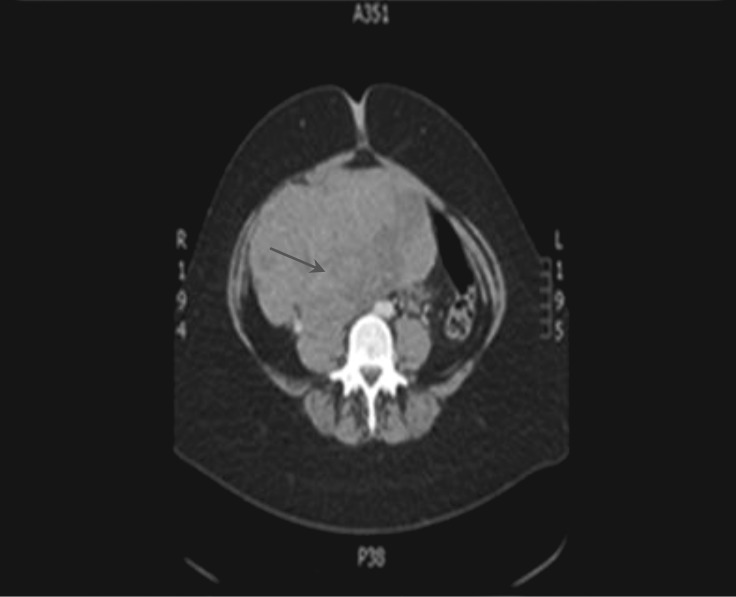

Unlabelled: Ectopic hormone secretion is a well-recognised phenomenon; however, ectopic prolactin secretion is exceptionally rare. Hoffman and colleagues reported the first ever well-documented case of ectopic prolactin secretion secondary to a gonadoblastoma. We report a lady who presented with galactorrhoea and a large ovarian tumour that was found to secrete high levels of prolactin.

Learning points: Aim of this case report is to highlight the occurrence of this condition.Lack of awareness can often lead to a diagnostic conundrum.